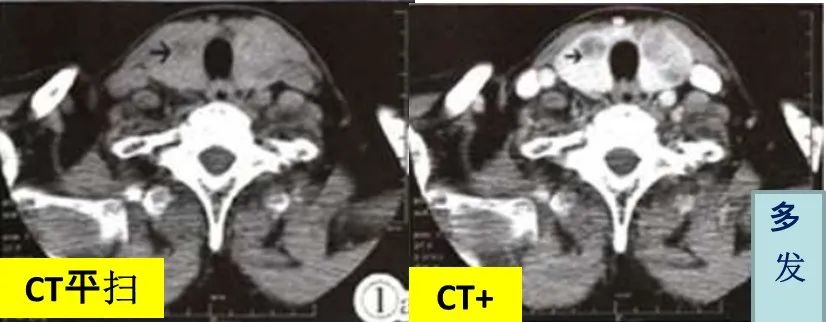

CASE 25 医学百科网 | YxBaike.Com

甲状腺左侧叶髓样癌,平扫边界清晰,增强后边界模糊 医学百科网 | YxBaike.Com